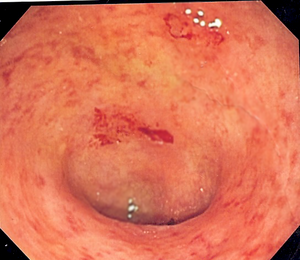

Endoscopic image of a sigmoid colon afflicted with ulcerative colitis. Note the vascular pattern of the colon granularity and focal friability of the mucosa. | |